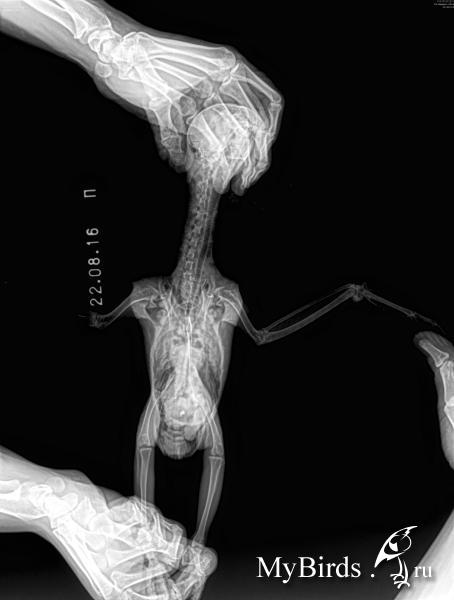

В январе начала обгрызать перья на крыле - буквально брала крыло в лапу и грызла, самец начал отгонять от кормушек, отсадили в отдельную клетку, через пару дней она вообще перестала есть. Когда взвесили, она весила 350 грамм, т.е. проблемы с едой были уже давно, но я недосмотрела. Начались проблемы с пометом. Давали энтерол, карсил, линекс, метионин, мезим, но-шпу, йогурт - уже не помню, что с чем и в какой дозировке. Пищеварение наладили. Птица была куплена за год до этого, у нее изначально слезились глаза, но анализ на микоплазмоз был отрицательный (сейчас я понимаю, что результат был неверный, или написан от фонаря). В начале февраля сдали опять в Бальде анализ на микоплазмоз, бакпосев, копрограмму, смыв на грибок из зева и глаза. Микоплазмоз был отрицательный, НО смутило то, что при явных нарушениях пищеварения копрограмма была идельной. В общем, этим анализам не верю. Еще появились проблемы с лапой, при ходьбе по ровной поверхности она подгибалась вовнутрь, если дать в лапу палец, то она его не отпускала. Врач предположил, что микоплазмоз все-таки есть и мы начали давать сумамед. Врач предложил два варианта лечения: сумамед в течение месяца или 2 недели сумамед + 2 недели макропен. Второй вариант он предложил как менее гепатотоксичный, и мы на него согласились. На сумамеде вначале было обострение в виде насморка (даже у второго попугая, у которого симптомов до этого никаких не было) а потом все наладилось, прошло слезотечение, а когда начали макропен - все началось снова. Кроме антибиотиков давали витамины В1, В6, В12, линекс, пимафуцин. Сустав на крыле воспалялся, под кожей как бы появлялась жидкость. Сдали анализы в государственной лаборатории, которая обслуживает птицефабрики. У Маши обнаружена микоплазма, а у второго попугая - микоплазма и орнитоз (у него симптомов никаких не было). Потом был доксициклин 6 недель. Он не помог - слезотечение сохранялось, сустав на крыле время от времени воспалялся. Врач предложил выждать как можно дольше и опять начать сумамед. В середине августа она опять начала грызть крыло, воспалился сустав, и 16 августа начали опять сумамед. Три дня назад появились небольшие хрипы при дыхании, а со вчерашнего дня дыхание очень затруднено. Колю дексаметазон по 0,04 - 4 раза в день. Анибиотик не отменяла. Сегодня поехали не рентген. Снимки прикреплены. Все это время, с февраля, птица практически не ест сама - у нее стоит в корме Престиж для жако, из которого она иногда выбирает семечки. Вес за первый месяц болезни набрали с 350 до 400 грамм, на этом набор остановился.

Это аспергиллез? Если да, то чем лечить и что делать с антибиотиком? Продолжать? Как лечить и аспергиллез, и микоплазмоз? Деньги на Вифенд найду.

По рентгену невозможно поставить диагноз аспергиллез.

Рентген который Вы прикрепили очень жесткий, в боковой проекции область грудных воздухоносных мешков нормально визуализируется.

У птицы нет одного крыла? или это такой снимок?